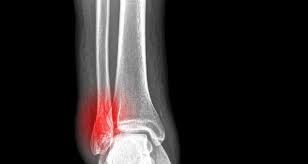

Bé 20 tháng tuổi rạn xương chày cẳng chân khoảng bao lâu hồi phục?

Bé nhà em 20 tháng bị rạn xương chày dưới cẳng chân, đi khám bác sĩ cho về không can thiệp gì, bác sĩ dặn bế cháu 3 đến 5 ngày rồi tự cho cháu đi lại. Bốn ngày rồi cháu không chịu đứng ạ! Bác sĩ cho cháu hỏi bé 20 tháng tuổi rạn xương chày cẳng chân khoảng bao lâu hồi phục? Em có cần cho bé kiểm tra lại không thưa bác sĩ? Rất mong bác sĩ tư vấn, em cảm ơn ạ!